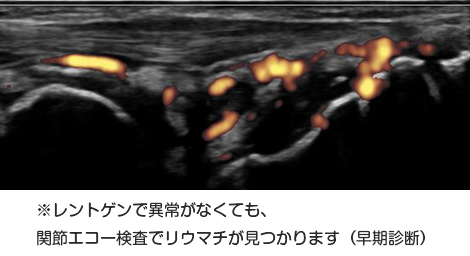

昔はレントゲンでリウマチの診断をしておりましたが、実はレントゲンでは骨しか見えないのです。

リウマチが最初に起きる肝心の関節の中は、残念ながらレントゲンでは写らないのです。そのためレントゲンでは早期のリウマチは診断がつかず、リウマチが進行して骨が壊れてから初めて診断となります。

そこで活躍するのが「関節エコー」です、エコーを関節の上にポンっとあてるだけで、関節の中に腫れ・炎症があるかが分かり、骨が壊れる前のリウマチの診断ができます。